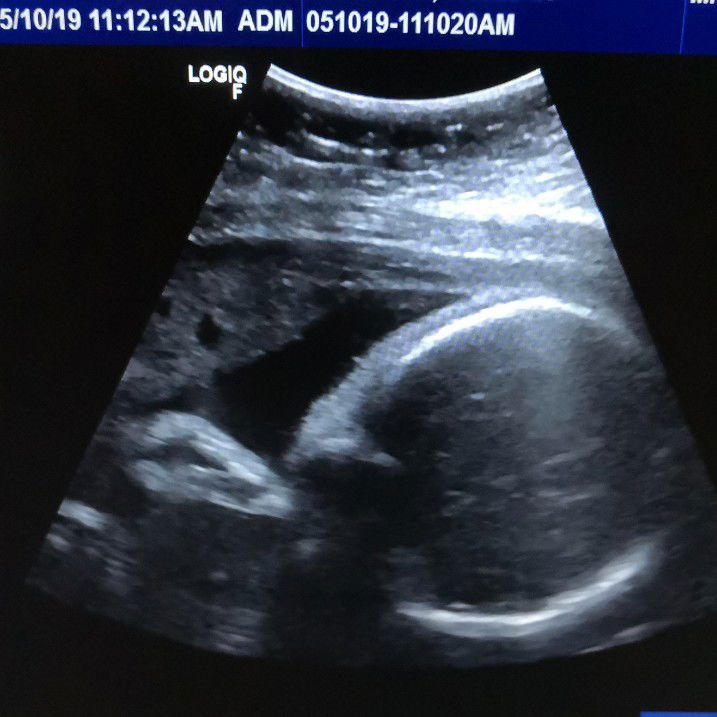

Medyo mahaba po, share ko lang at may questions din po ako sa dulo. 2016 nadetect na pre-diabetic na ako at may pcos na rin. Sobrang irregular ng period ko na ung pinakamatagal june2017-January2018 na hindi ako nagkaron. Until one day nakita kong nakakapagpa regulate ng hormones ang GLUTATHIONE so nagstart ko syang itake November2017-January2018 hanggang nagkaroon na ako uli at naging regular na period ko. February2018 we're having almost everyday lovemaking trying to conceive hanggang lumipas mga months nagkakaperiod pa rin ako. Hanggang tumigil uli period ko ng September2018 at di na naman bumalik. Nawalan na kami ng pag-asa kasi negative PT ko nung November2018 at December2018.. Umuwi muna ako sa pinas ng april2019 to relax kasi baka sobrang stressed out ako sa work.. 1 week before ako umuwi, naramdaman kong may pumipitik sa tyan ko. Akala ko sumasabog na ovaries ko ?? so I've decided to make an appointment sa hospital may10,2019 medyo nalate kasi natatakot ako na baka may sakit ako. Sinabi kong may pcos ako kaya transV ang ginawang ultrasound sakin. Sobrang kabado ako kasi baka cancer na ? ayun na nga, humiga na ako at chineck muna ng nurse initial. Convo: Nurse: ma'am, malaki na po ito. Me: what? May bato ba? Cancer? Mamamatay ba ako? Nurse: relax ma'am. Hindi at wala po. Me: eh ano ung malaki? Tyan ko? Alam ko na un kasi mataba talaga ako hehe Nurse: ma'am yung malaki po ay ung baby nyo. Magrequest lang po ako ng tamang ultrasound nyo. Umalis si nurse at eto ung nakaPause sa monitor. I'm shocked and worried kasi 33weeks na si baby nung malaman ko, maliit daw sya at medyo mataas ng konti amniotic fluid. Walang signs ng pregnancy bukod sa naging antukin ako at naging matakaw. Questions: 1. May naka experience na po ng ganito? And how's your baby paglabas? 2. Pcos and Gestational diabetes, Normal or CS po kayo? 3. Regarding Vitamins, is it too late? 33weeks na ako nakapag start now im 38weeks. 4. Possible ba sa autism or any complications si baby? Eyes, nose, lips, arms, legs, brain Appears Normal naman po lahat. Pero natatakot pa rin ako kasi Coffee ako halos everyday, fast food, had beer twice, smoked 15sticks, Panadol Extra, Cough syrup, flu medication, na food poison din ako nung feb2019. Asking for your prayers na rin po. I'll be praying for you too β€οΈ